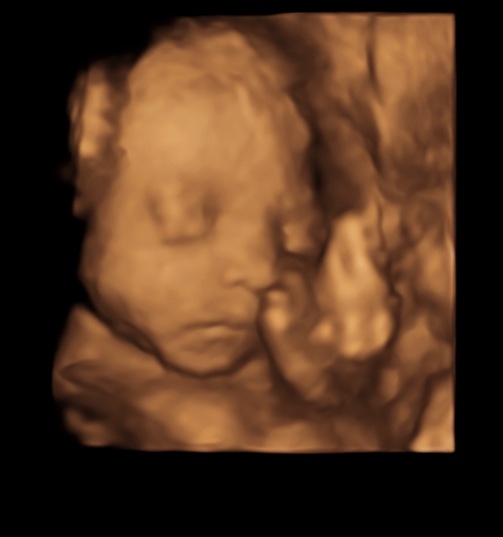

Here’s one of my 4D pictures her little face 🥺

@Babyhope98 Oh my goodness what a cute little face!!

Gorgeous @Babyhope98 ☺️❤️

@Babyhope98 Awh that's gorgeous!!

@babyhope98 That is a beautiful image!!